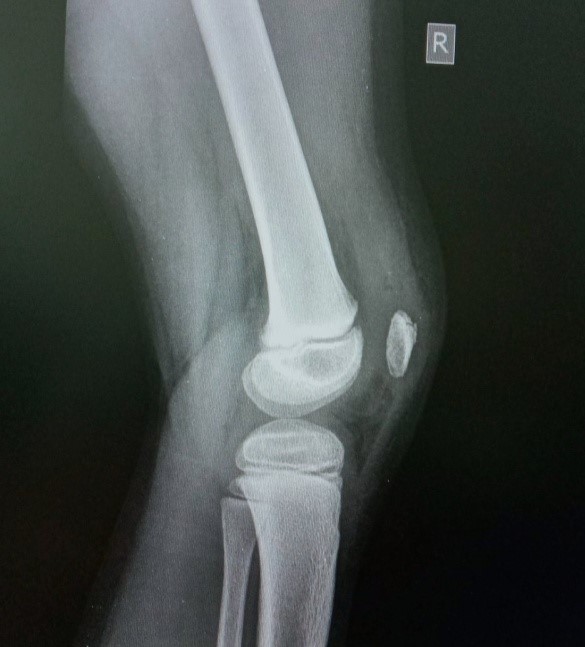

Перелом шейки бедра (перелом шейки бедренной кости) - тяжелая и опасная травма, которая может возникать как у пожилых, так и у молодых людей . Что такое шейка бедра и где находится?